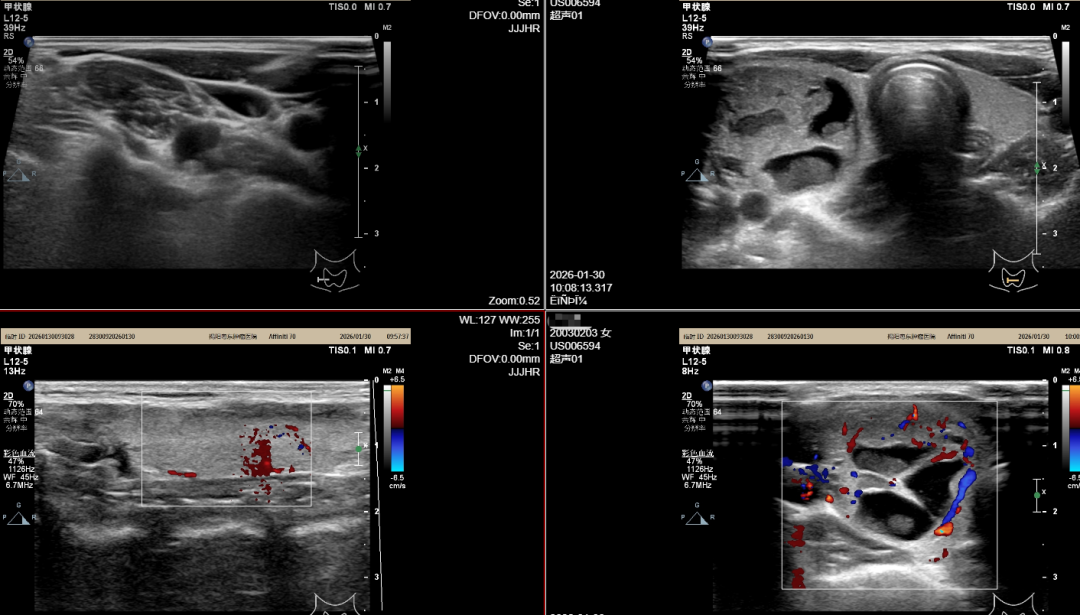

患者为22岁女性,因“发现甲状腺结节5年”入院。该名患者于5年前因喉咙疼痛在当地医院就诊,检查超声发现甲状腺结节,服用中药治疗后,复查结节较前有缩小。于半年前因发现脖颈增粗,复查发现甲状腺结节增大,无疼痛、无咳嗽、无吞咽异常等情况,为求进一步治疗,来我院就诊。

影像学报告显示患者甲状腺右侧叶可见一大小约36mm x 24mm x 22mm、边界清楚、形态尚规则、以液性回声为主的囊实混合性结节,最终我院为其施行了甲状腺结节微波消融术,术后颈部仅可见微小针孔。